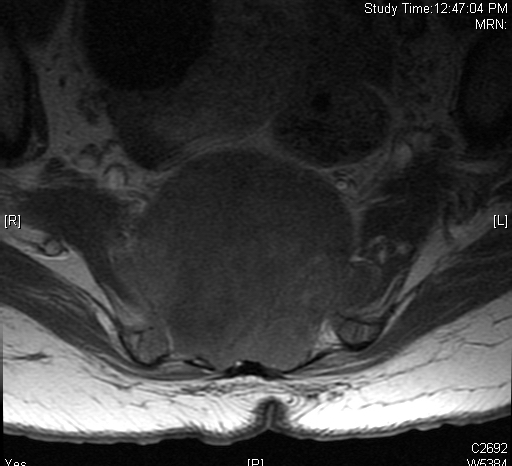

MRI (Fig. 4-10)

• Hyperintense on T2W (Fig. 8 & 9)

Fig. 4-10: MR image of a chordoma shows a destructive bone lesion in the sacrum that is hypointense on T1W images, hyperintense signal on T2W and enhancement of the lesion after gadolinium.